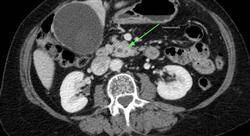

تشمل جراحة القناة الصفراوية بشكل أساسي العلاج الجراحي لتحصي الصفراوية وتحصي القناة الصفراوية والخراجات والتهاب الأقنية الصفراوية المصلب الأولي وأورام القناة الصفراوية والمرارة. سمح التقدم التشخيصي والمعرفة الأفضل بالفيزيولوجيا المرضية للأمراض الكبدية بتقدم غير عادي في علاج هؤلاء المرضى، خاصة فيما يتعلق بتطوير استئصال المرارة بالمنظار، وهو أحد أكثر التدخلات التي تم إجراؤها في بيئتنا من قبل معظم الجراحين العامين.

تقديم ورش عمل عملية حول الإجراءات الجراحية والتقنيات التشخيصية والعلاجية للأمراض الصفراوية الرئيسية، مثل تحص صفراوي وتحص القناة الصفراوية، والخراجات والتهاب الأقنية الصفراوية المصلب الأولي وأورام القناة الصفراوية والمرارة